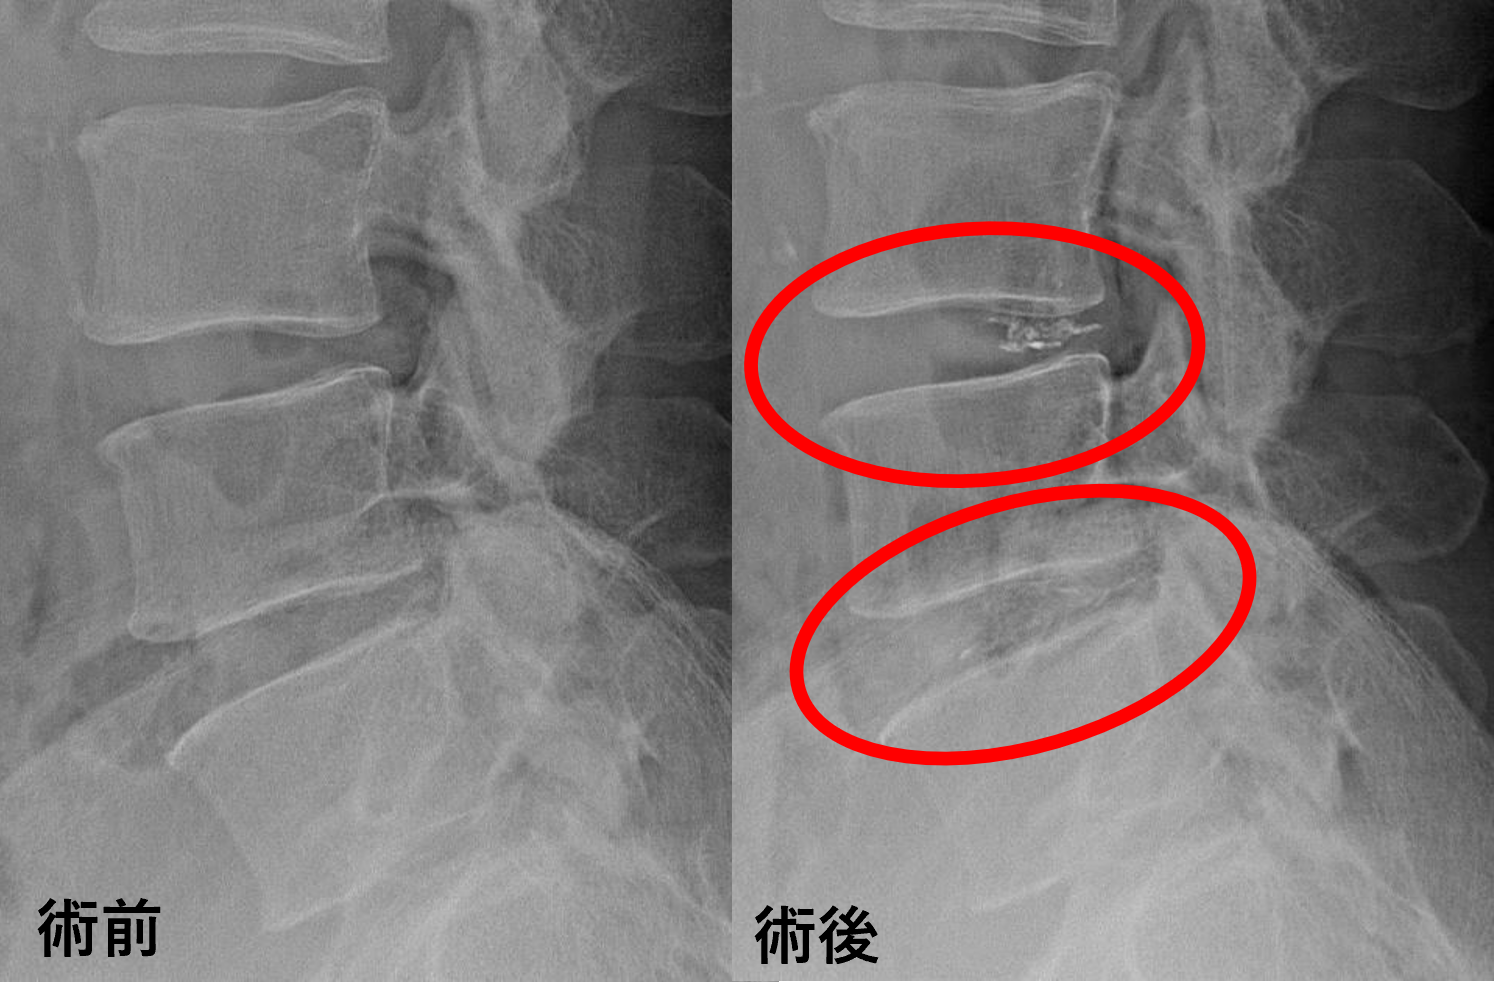

画像及び所見について

- L4/5 – 椎間板変性、膨隆

- L5/s – 椎間板変性、膨隆、繊維輪断裂

以上のことが画像上認められました。

L4/5、5/sの椎間板所見による脊柱管の圧排が、症状の原因の可能性が高い。

患者様と相談の元、L4/5、5/sにセルゲル法を施行